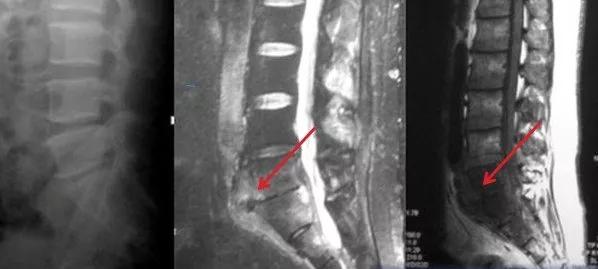

2、这是一个成年男性患者,因轻微背痛就诊。影像检查发现脊柱结核。从核磁看(红色箭头示)胸椎多节段椎前脓肿,但椎体和椎间隙狭没有明显炎性病变或破坏。

这属于“骨膜下型”脊柱结核,可以采取保守治疗。制定抗结核治疗方案后,定期随诊复查。

抗结核治疗六个月后,脓肿吸收不明显(红色箭头示)。

患者背痛仍不明显,椎体和椎间盘也无破坏。继续保守治疗,但调整抗结核药物,重新组合药物方案。用药一年后,脓肿完全吸收(红色箭头示)。病灶愈合。